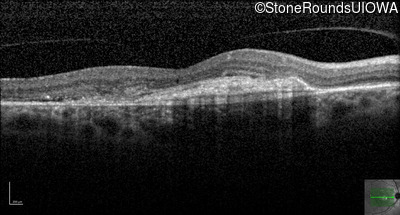

Age at visit: 59 years (Visit 3)